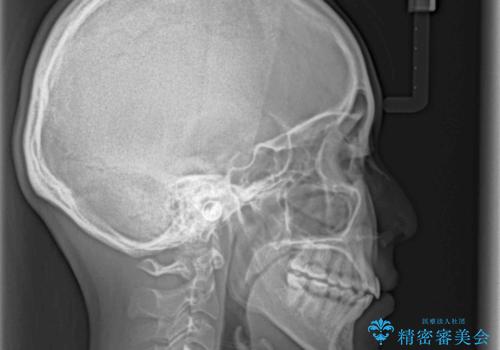

- 前歯のでこぼこと乳歯が残るほどの八重歯を気にして来院された患者様です。

非抜歯にてワイヤー矯正にて治療することとしました。(ただし、親知らずと乳歯は抜歯)

犬歯は歯根が太く長いため、移動には時間を要します。しかし、犬歯は機能面から考えて残すことを選択したいため、長期間をかけて治療を行うこととしました。

治療の度に歯列が改善していったため、長期間の治療も楽しく過ごしていいただき、満足のいく仕上がりとなりました。